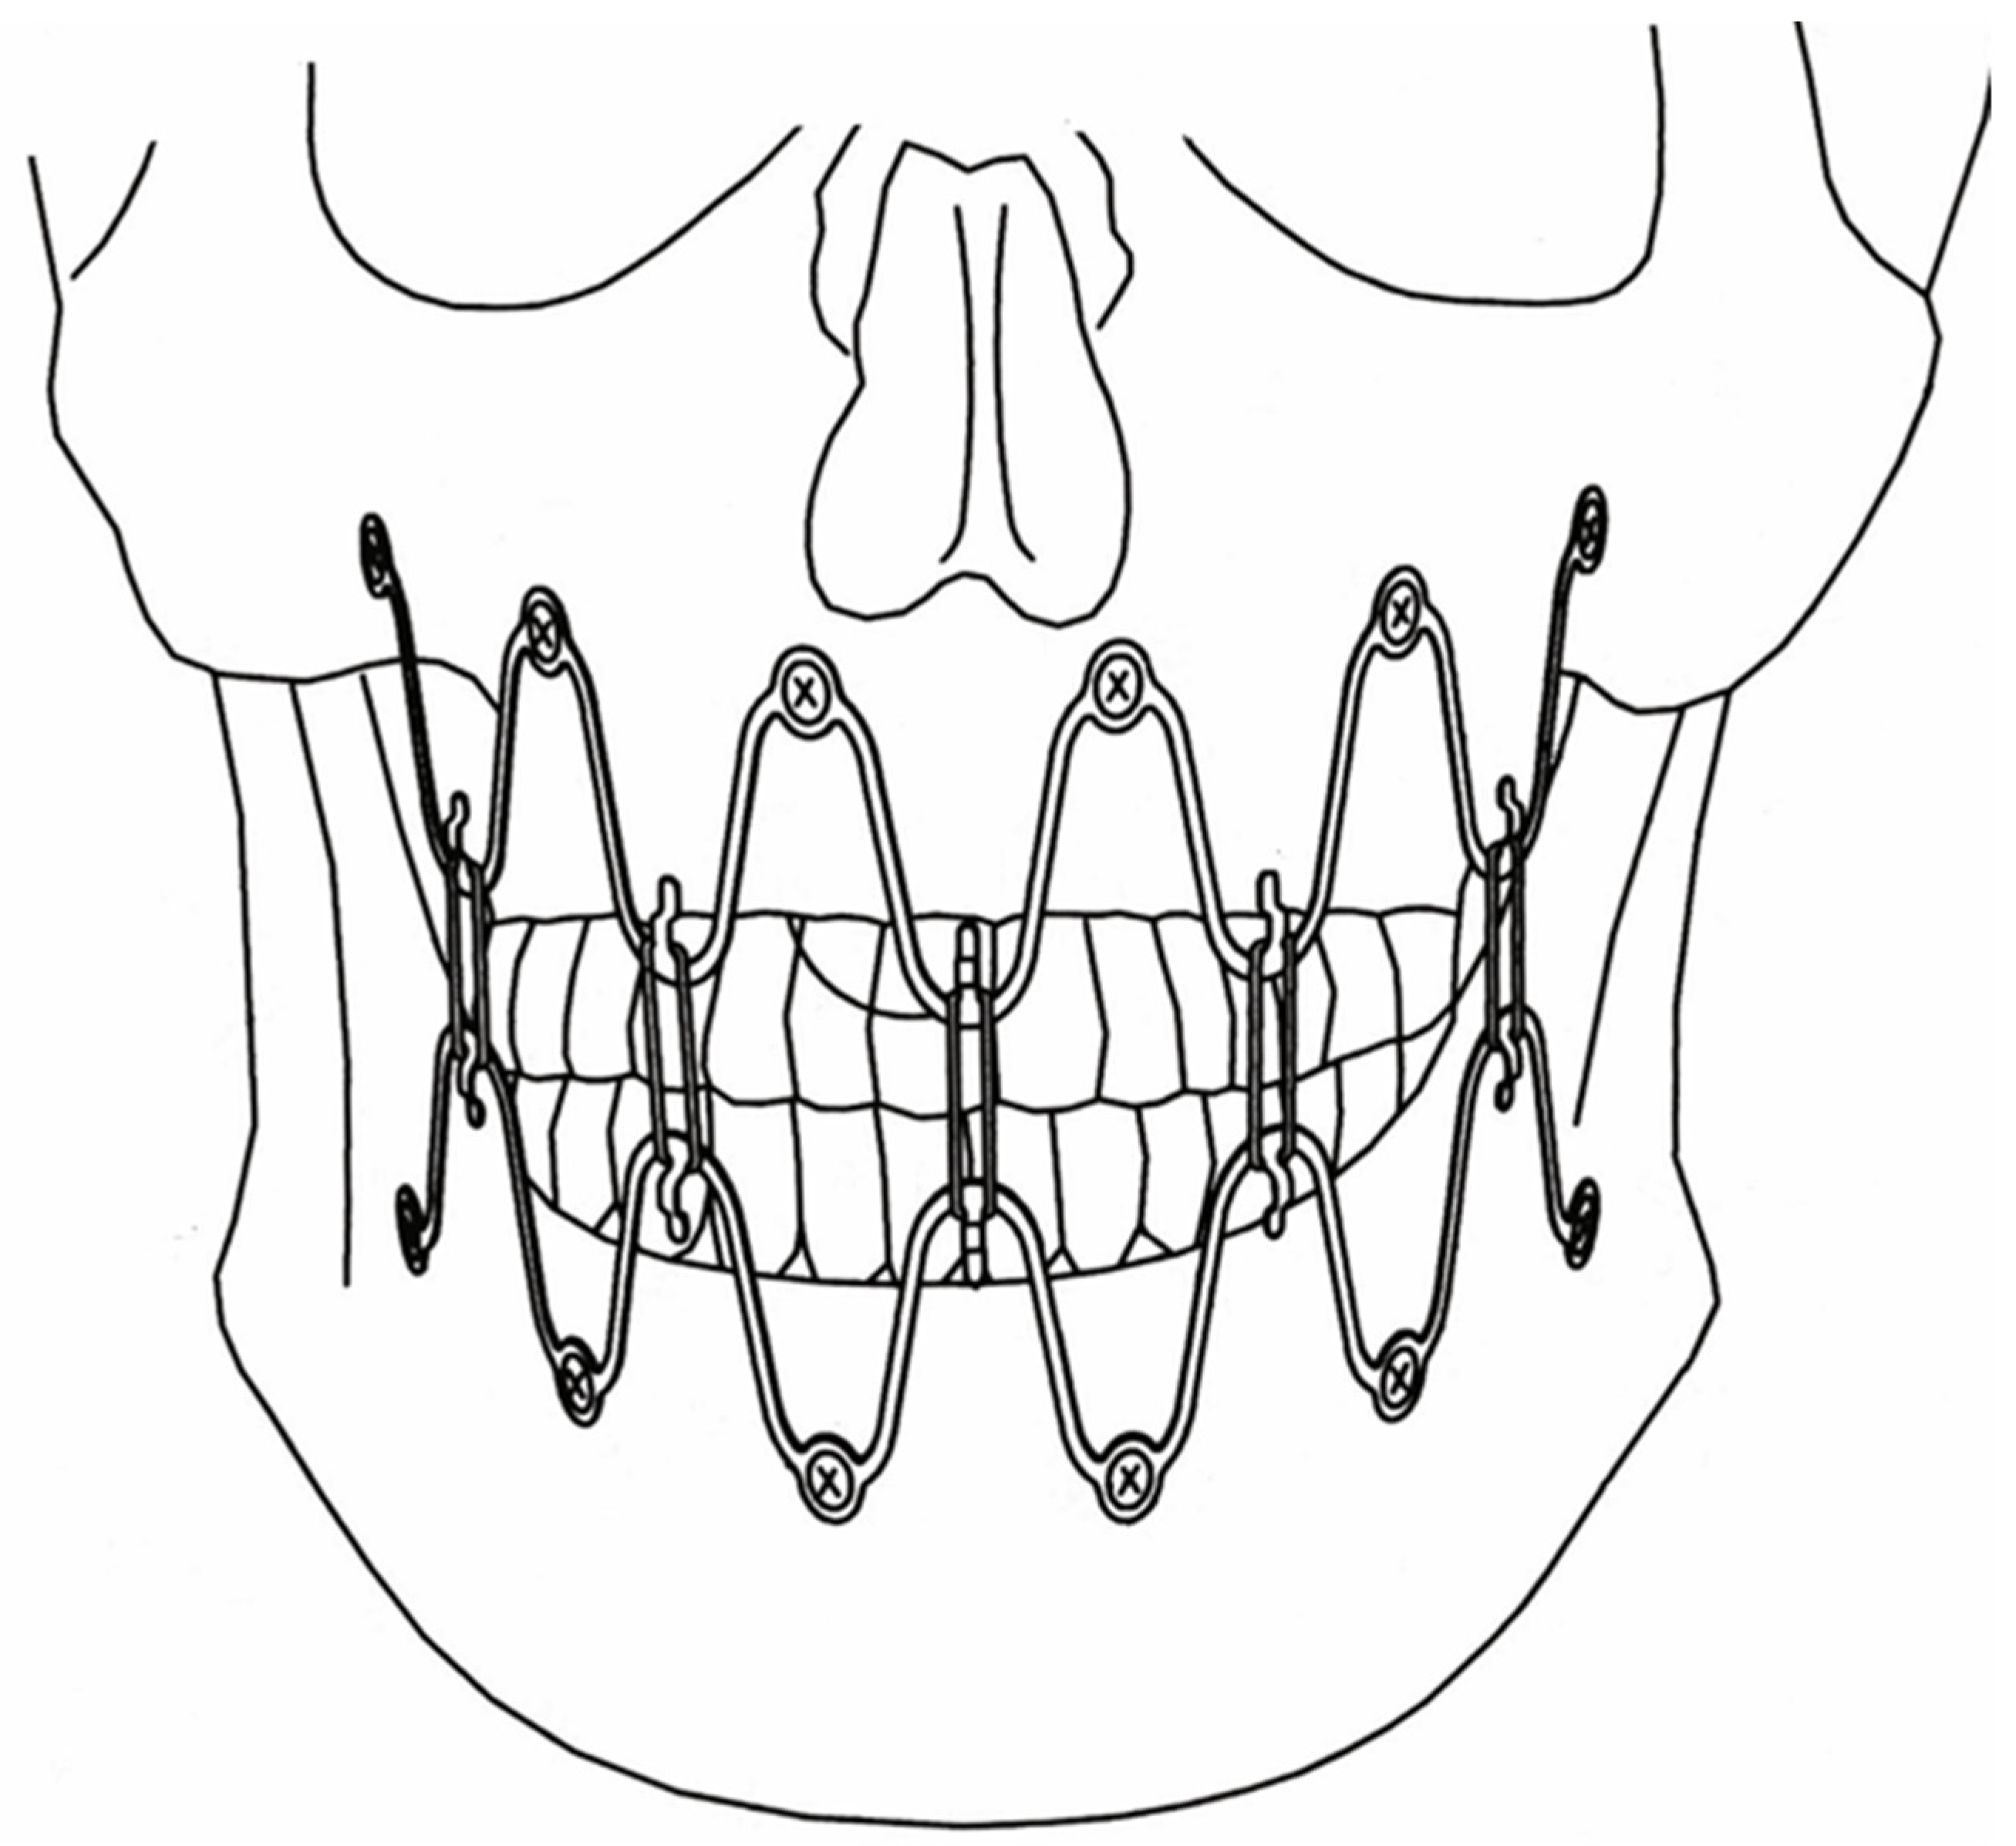

3.2. Matrix WaveTM Plate MMF System—Mode of Application